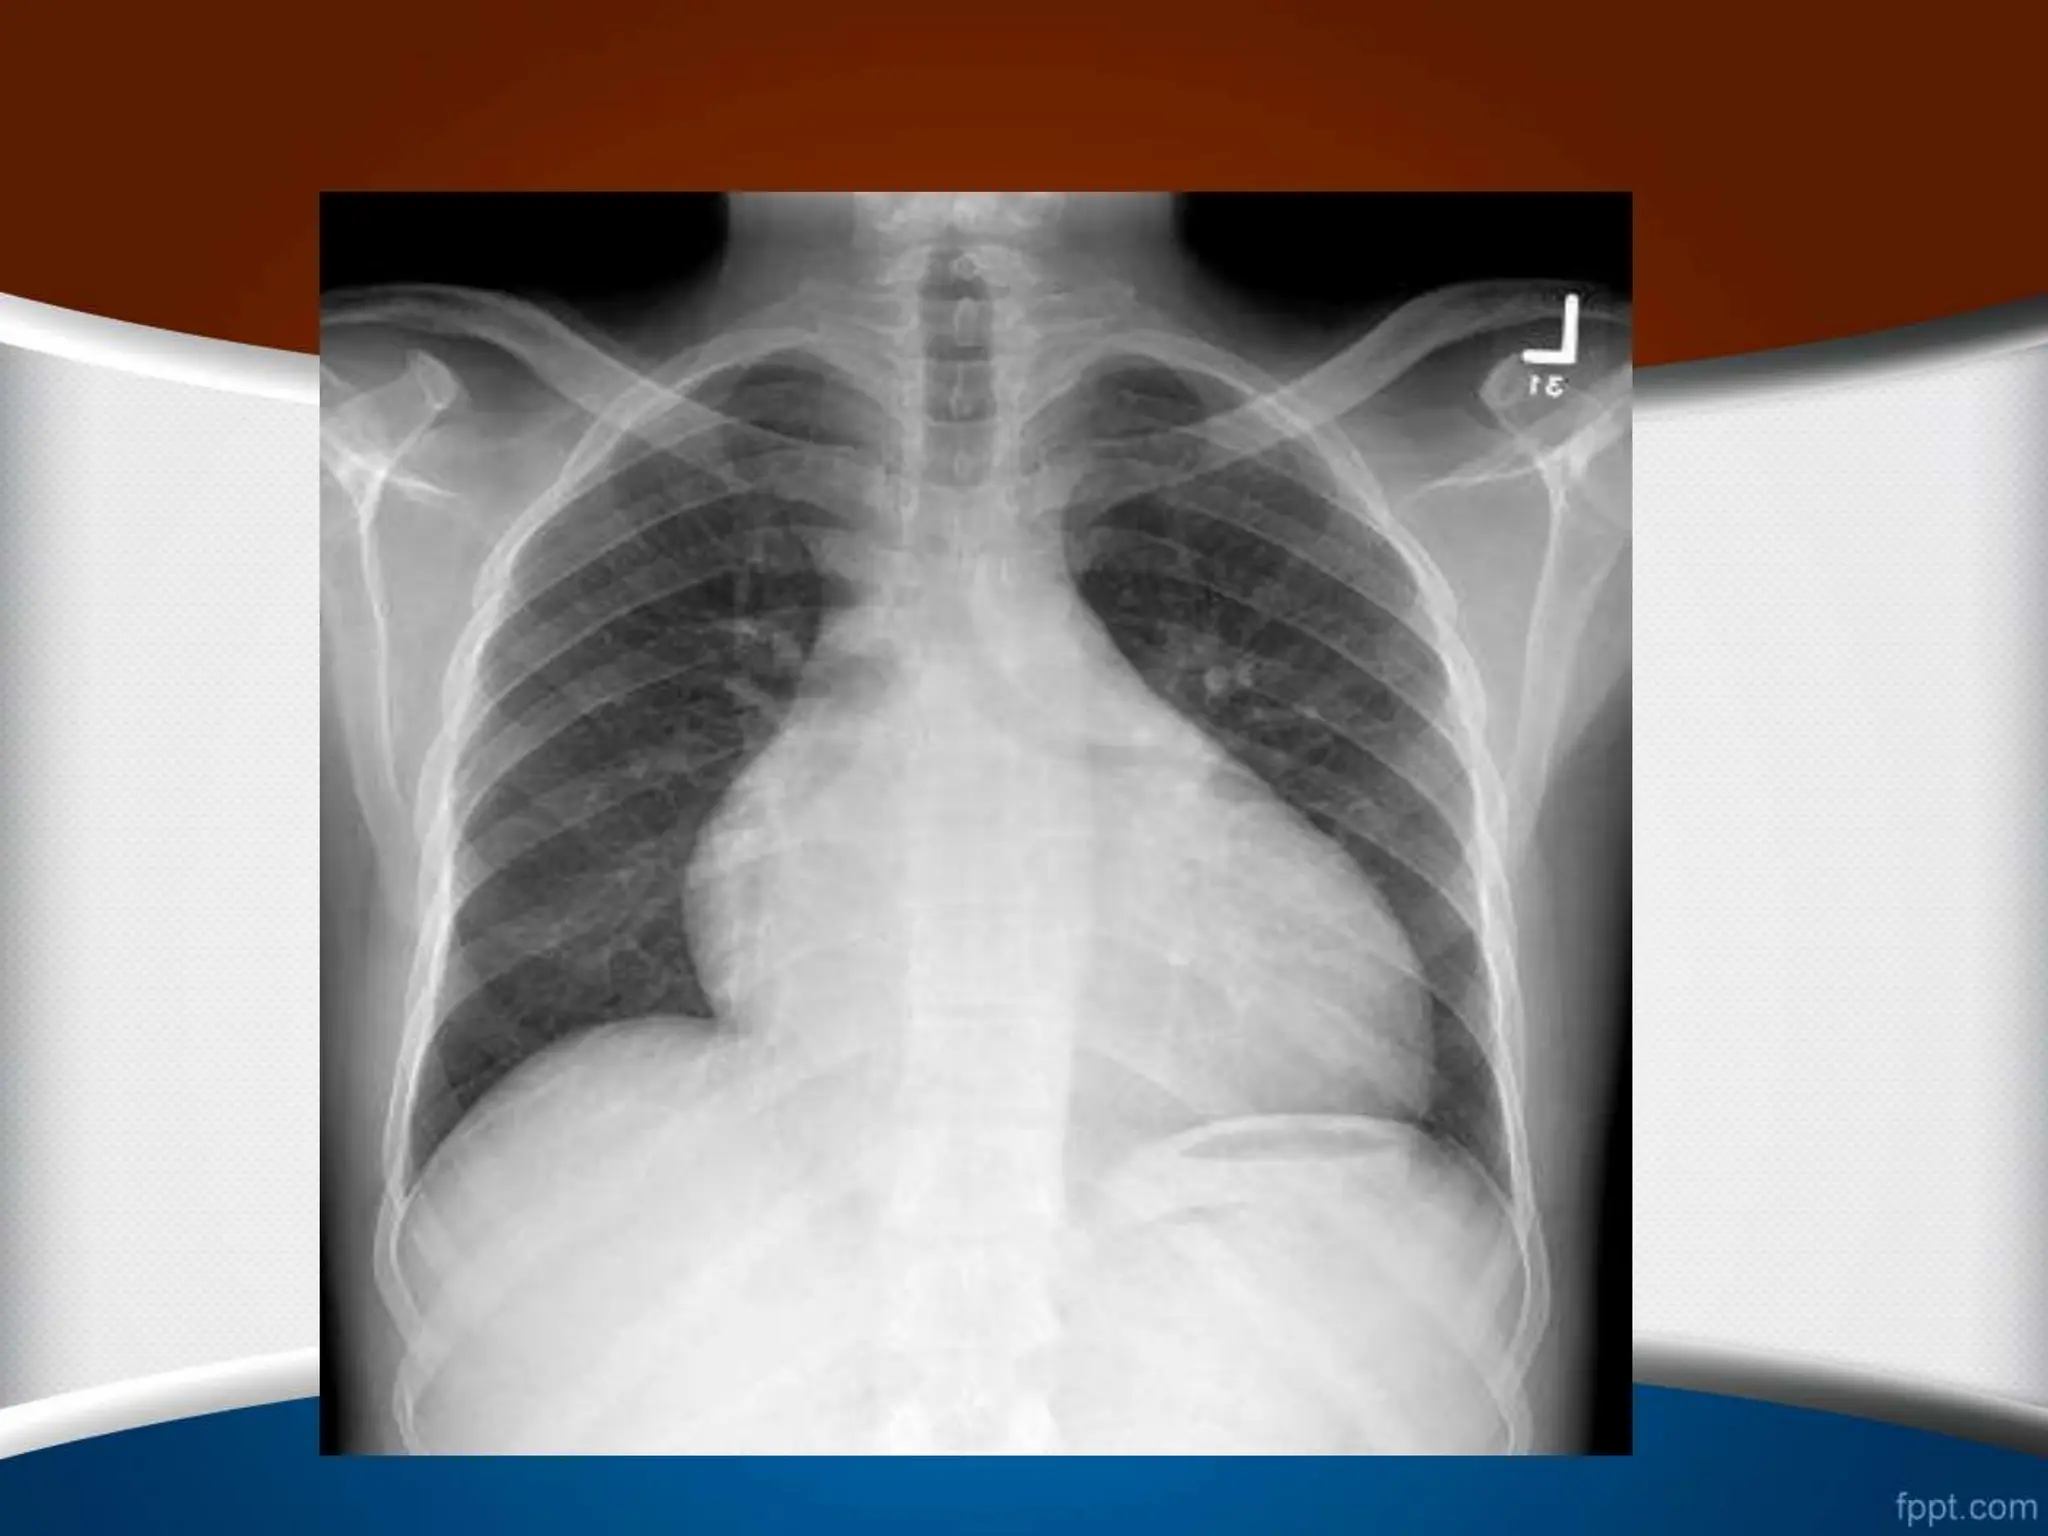

‫قلب‬ ‫ی‬ ‫اندازه‬

•

‫کاردیوتوراسیک‬ ‫نسبت‬ ‫نرمال‬ ‫حالت‬ ‫در‬

(

CTR

)

‫افراد‬ ‫در‬

‫از‬ ‫کمتر‬ ‫بالغ‬

50

%

‫است‬

.

‫این‬ ‫مسن‬ ‫افراد‬ ‫و‬ ‫کودکان‬ ‫در‬

‫نسبت‬

‫تا‬

55

‫باشد‬ ‫می‬ ‫قبول‬ ‫قابل‬ ‫هم‬

‫قلب‬ ‫ی‬ ‫اندازه‬ • ‫کاردیوتوراسیک‬‫نسبت‬ ‫نرمال‬ ‫حالت‬ ‫در‬ ( CTR ) ‫افراد‬ ‫در‬ ‫از‬ ‫کمتر‬ ‫بالغ‬ 50 % ‫است‬ . ‫این‬ ‫مسن‬ ‫افراد‬ ‫و‬ ‫کودکان‬ ‫در‬ ‫نسبت‬ ‫تا‬ 55 % ‫باشد‬ ‫می‬ ‫قبول‬ ‫قابل‬ ‫هم‬ . •